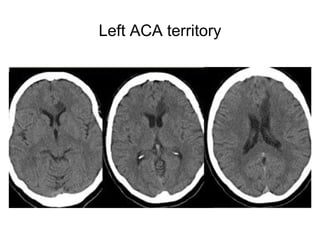

Left ACA territory